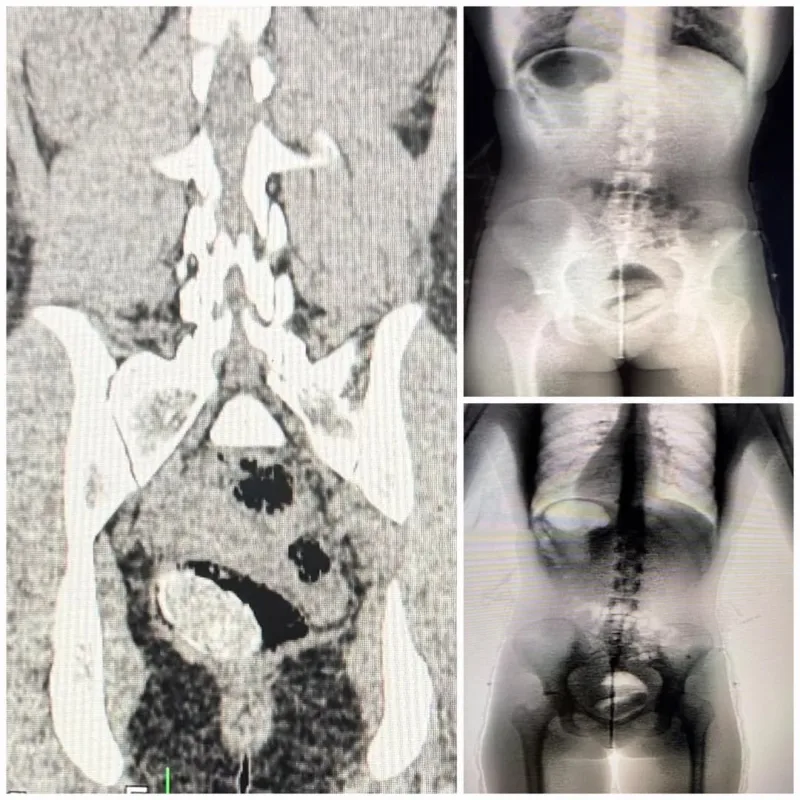

Uma visitante foi flagrada tentando entrar com material ilícito no Conjunto Penal de Irecê durante o horário de visitação nesta quarta-feira (15). A suspeita foi identificada após o equipamento Body Scan apontar uma anormalidade durante o procedimento de revista.

Diante do alerta, a mulher foi encaminhada ao Hospital Regional de Irecê para a realização de exames complementares. A avaliação médica confirmou a presença de material ilícito ocultado em cavidade corporal.

Após os procedimentos, foi constatado que se tratava cocaína, acondicionada para ocultação interna. Em seguida, a envolvida foi conduzida à 14ª Coordenadoria Regional de Polícia do Interior, onde foram adotadas as medidas legais cabíveis.